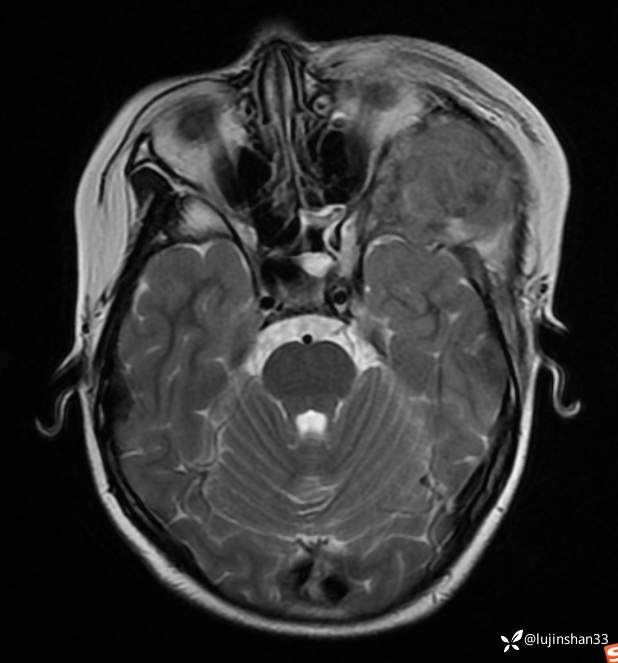

2021年8月复查MRI